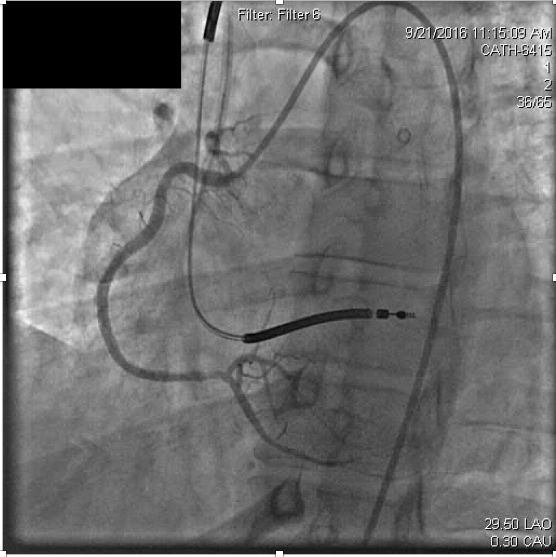

Myocardial infarctionin patients under the age of 45 is considered rare occurring in approximately 6-10% of the general population. In many cases, premature coronary atherosclerosis plays an important causative role, however about 20% of young adult coronary thrombosis can be attributed to hypercoagulability. In this article, we present a 43 year old patient with recurrent coronary thrombosis. While an initial presentation of acute myocardial infarction appeared driven by common re-thrombosis and acute stent thrombosis revealed a hypercoagulable state. This case highlights challenges in management of acute myocardial infarction and hypercoagulable states. It emphasizes the vigilance that must be exercised in generating differential diagnoses for coronary thrombosis.References